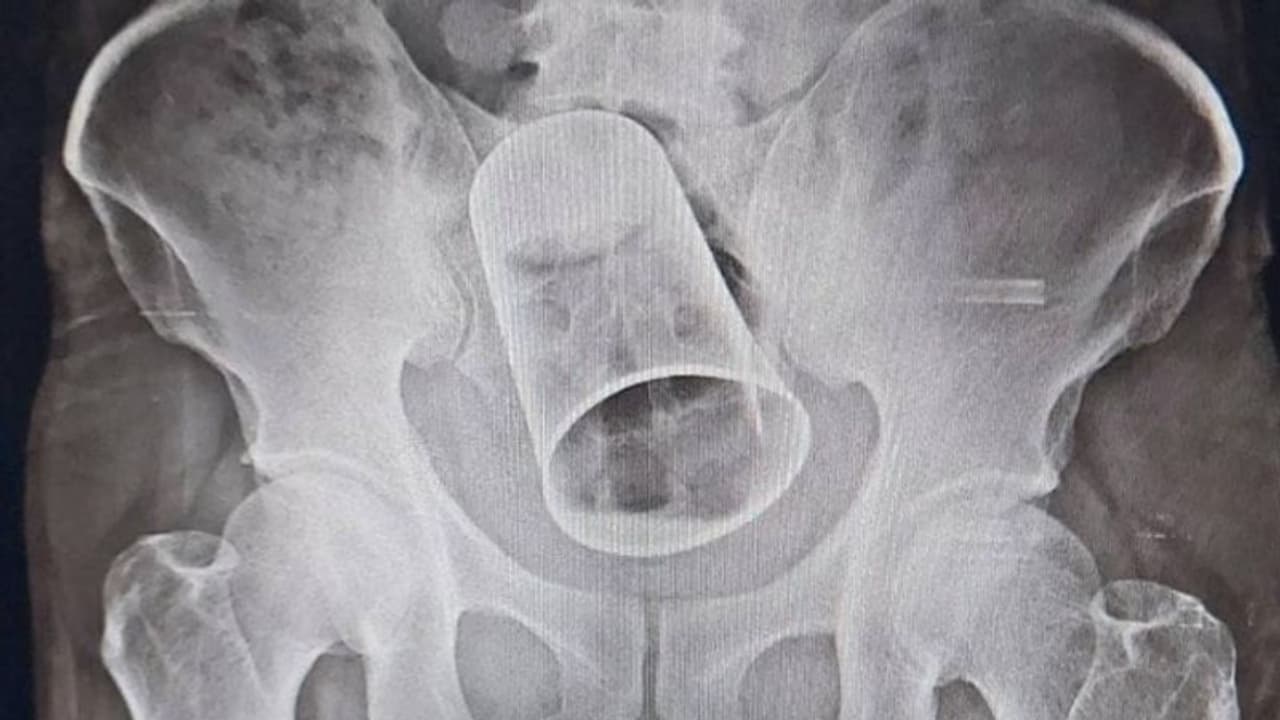

എന്നാല് എക്സറേ പരിശോധനയില് യുവാവിന്റെ ശരീരത്തിനുള്ളില് സ്റ്റീല് ഗ്ലാസ് കുടുങ്ങികിടക്കുന്നത് ഡോക്ടര്മാര് കണ്ടെത്തി. ഇതോടെയാണ് കൃഷ്ണയുടെ സുഹൃത്തുക്കള് ചെയ്ത കൊടും. ക്രൂരത പുറത്തായത്. യുവാവിനെ ചികിത്സിച്ച ഡോക്ടര്മാര് മലദ്വാരത്തിലൂടെ ഗ്ലാസ് പുറത്തെടുക്കാന് ശ്രമിച്ചെങ്കിലും ഫലംകണ്ടില്ല. പിന്നീട് യുവാവിനെ ശസ്ത്രക്രിയയ്ക്ക് വിധേയനാക്കുരയായിരുന്നു. ആശുപത്രിയിലെ ശസ്ത്രക്രിയ വിഭാഗം മേധാവി പ്രൊഫ. ഡോ. ചരണ് പാണ്ഡയുടെ നേതൃത്വത്തിലാണ് ശസ്ത്രക്രിയ നടത്തിയത്. യുവാവ് സുഖംപ്രാപിക്കുന്നുവെന്ന് ഡോ. ചരണ് പാണ്ഡെ ദേശീയ മാധ്യമത്തോട് പ്രതികരിച്ചു.

ഭുവനേശ്വര്: ഗുജറാത്തില് യുവാവിനോട് സുഹൃത്തുക്കളുടെ കൊടും ക്രൂരത. മദ്യലഹരിയില് സുഹൃത്തുക്കള് യുവാവിന്റെ സ്വകാര്യ ഭാഗത്തുകൂടെ സ്റ്റീല് ഗ്ലാസ് കുത്തിക്കയറ്റി. പത്ത് ദിവസം മുമ്പ് ഗുജറാത്തിലെ സൂറത്തിലാണ് സംഭവം. കൃഷ്ണ റൗട്ട് എന്ന യുവാവിനെ ഒപ്പം മദ്യപിച്ച ശേഷം സുഹൃത്തുക്കള് ചേര്ന്ന് ആക്രമിക്കുകയായിരുന്നു. കടുത്ത വേദനയുമായി സ്വന്തം നാടായ ഭുവനേശ്വരിലെത്തിയ യുവാവിനെ പത്തുദിവസത്തിന് ശേഷം ശസ്ത്രക്രിയയിലൂടെ ശരീരത്തിനുള്ളില്നിന്ന് ഗ്ലാസ് പുറത്തെടുത്തു.

ഒഡീഷയിലെ ബെര്ഹാംപുര് എം.കെ.സി.ജി. മെഡിക്കല് കോളേജ് ആശുപത്രിയില് നടന്ന ശസ്ത്രക്രിയയിലാണ് ഗഞ്ചാം സ്വദേശി കൃഷ്ണ റൗട്ടി(45)ന്റെ ശരീരത്തിനുള്ളില്നിന്നും സ്റ്റീല് ഗ്ലാസ് പുറത്തെടുത്തത്. യുവാവ് സുഖംപ്രാപിച്ച് വരികയാണെന്നും ആരോഗ്യനില തൃപ്തികരമാണെന്നും ആശുപത്രി അധികൃതര് അറിയിച്ചു. സൂറത്തില് ജോലിചെയ്യുകയായിരുന്ന കൃഷ്ണ സുഹൃത്തുക്കള്ക്കൊപ്പം മദ്യപിക്കാറുണ്ടായിരുന്നു. സംഭവ ദിവസവും കൃഷ്ണ സുഹൃത്തുക്കള്ക്കൊപ്പം മദ്യപിച്ചിരുന്നു.